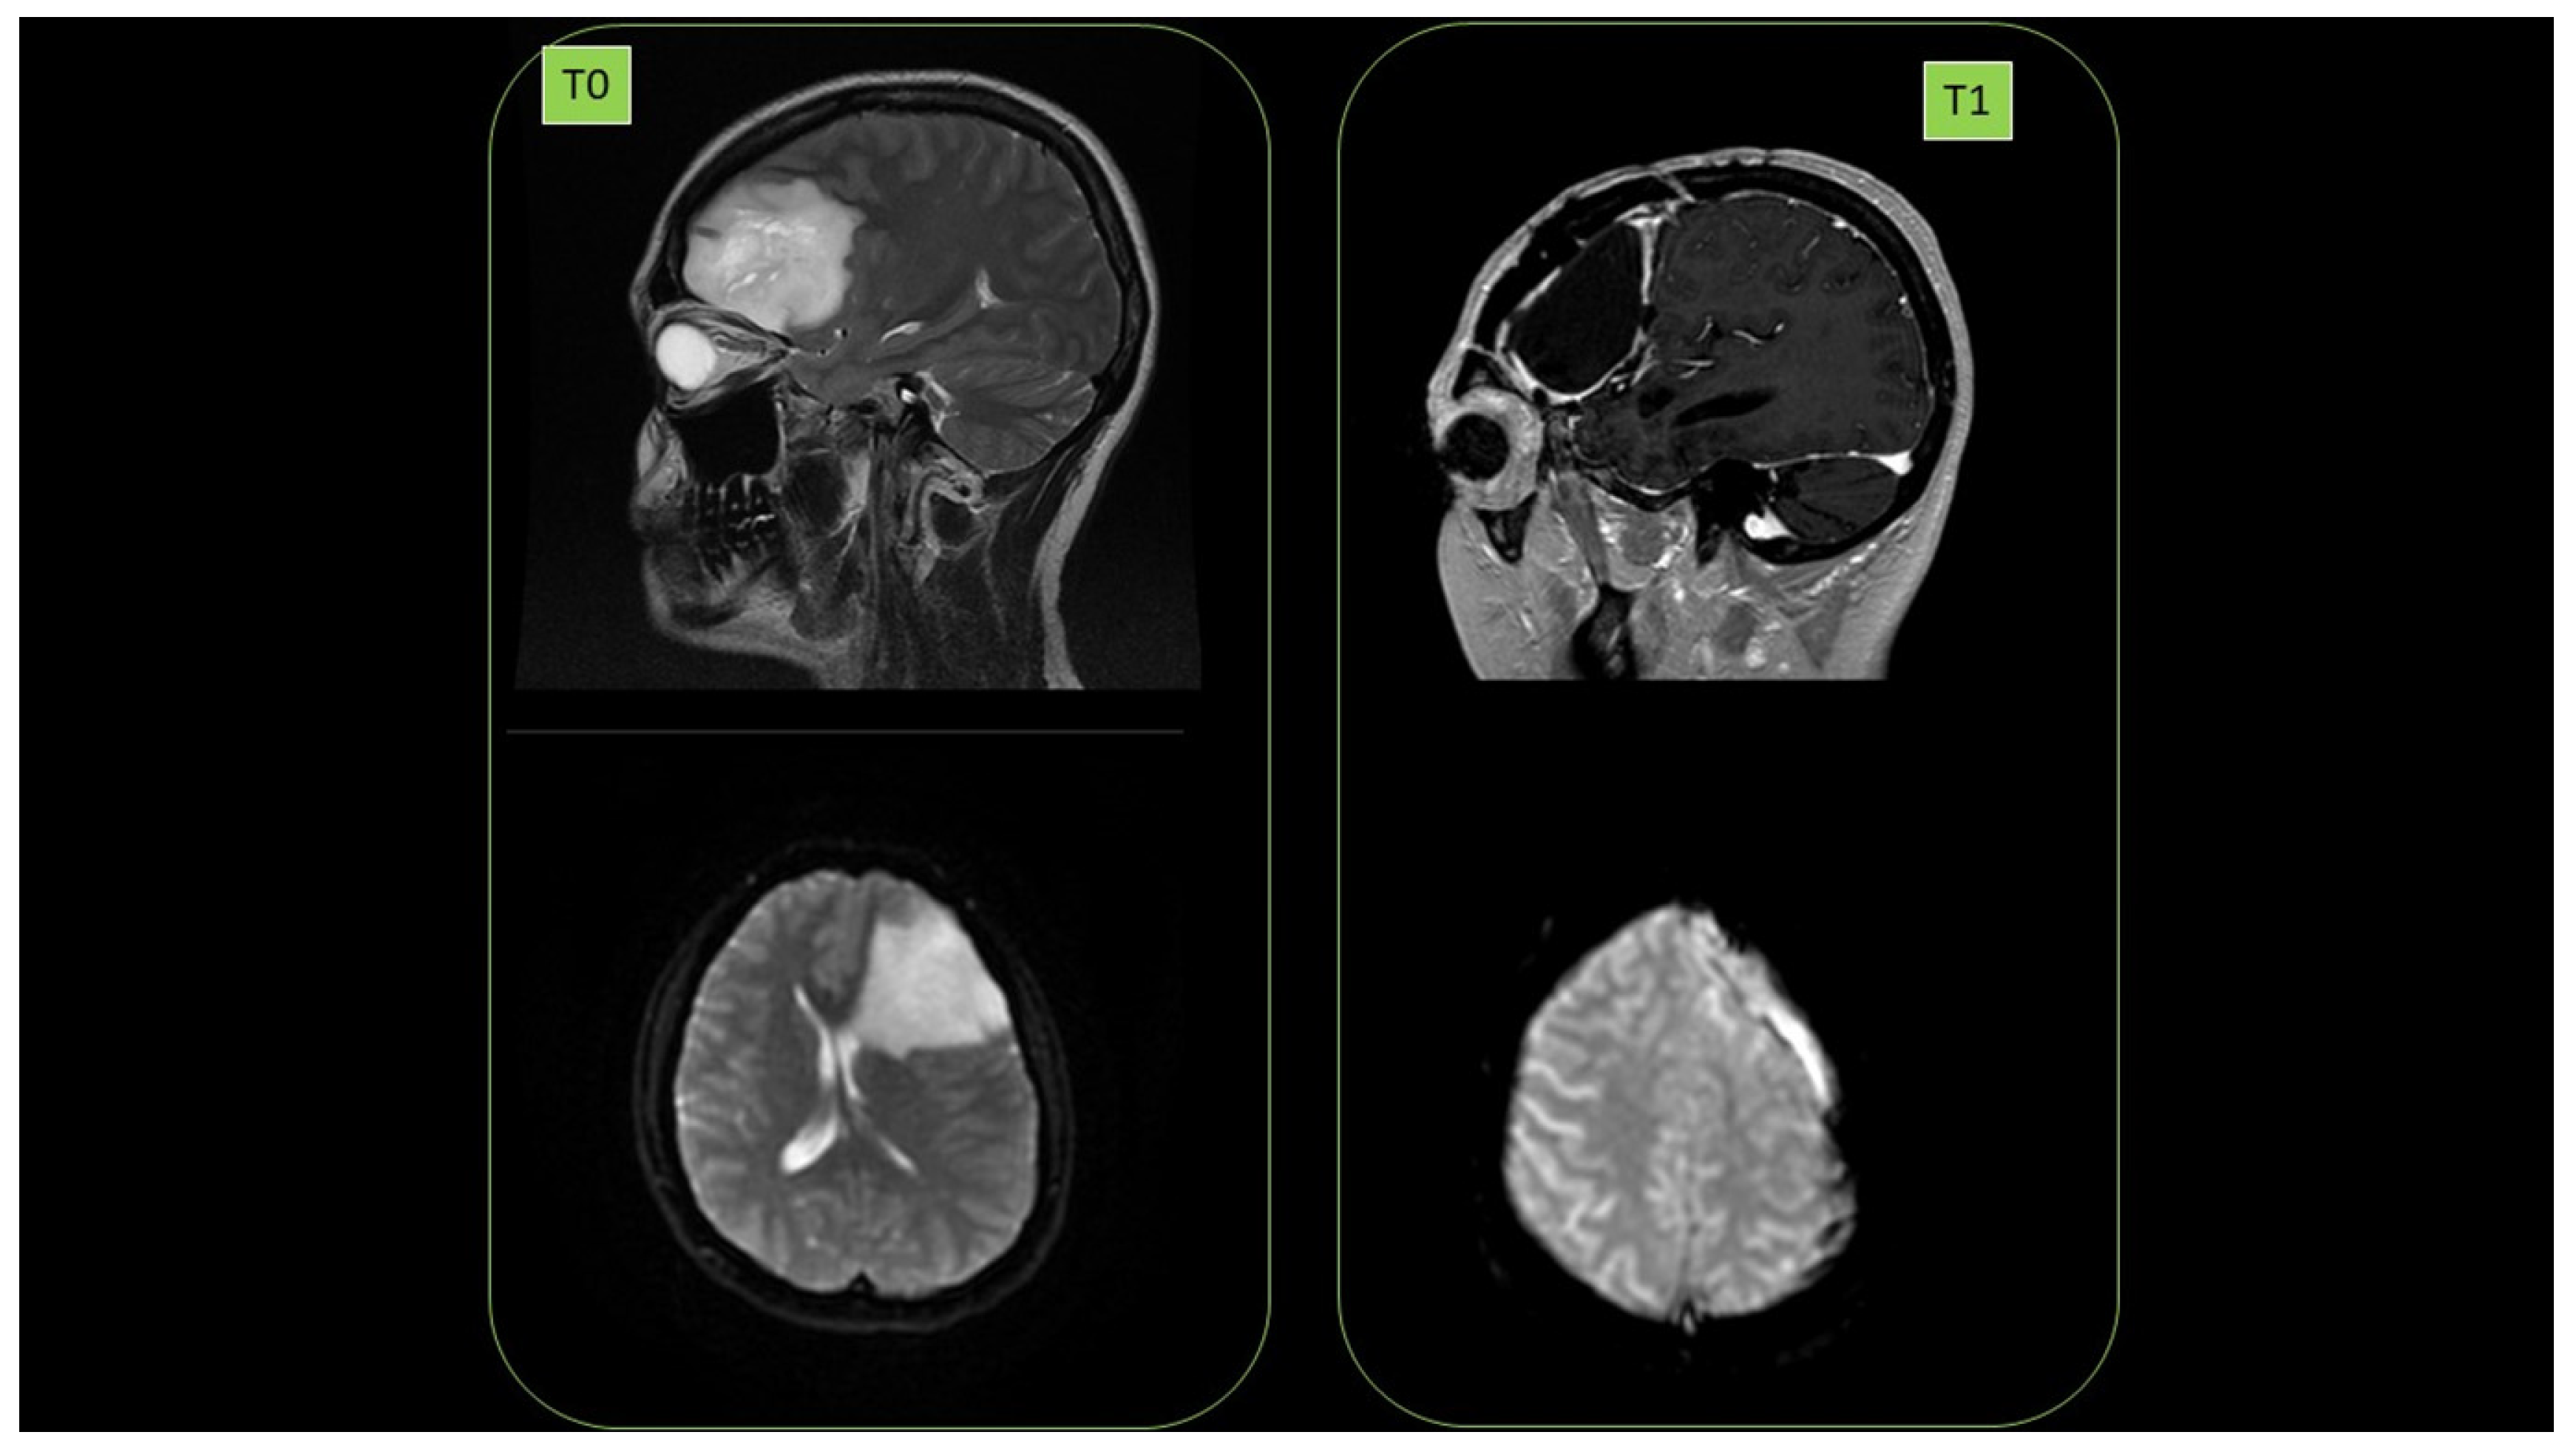

Female subject was a 38-year-old affected by brain glioblastoma in left hemisphere (diagnosis July 2014. 1st NMR, (T0)). First surgery was performed in September 2014. High malignancy (grade III) was observed. In May 2017, relapses (2nd NMR) were detected, and in June 2017, there was a second surgery. September 2017 radiotherapy (60 Gy) in parallel with the start of ozonized oil therapy (oral administration, 6 mL per day) was performed. No relapse (September 2018) was detected (3rd NMR, T1). Cancer presence at T0 as well as its clearance at T1 are reported in Figure 17.

Figure 17. Disappearance of radioresistant brain glioblastoma (T0) after 1 year of HOO treatment (T1), as detected by nuclear magnetic resonance in a 38-year-old female patient.